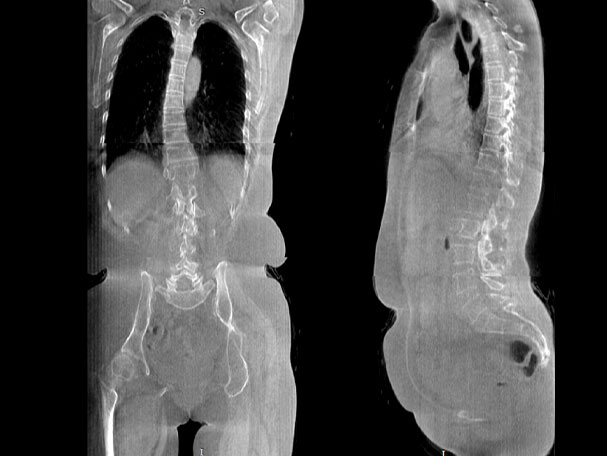

腰椎

FOV 250mm

FOV 350mm